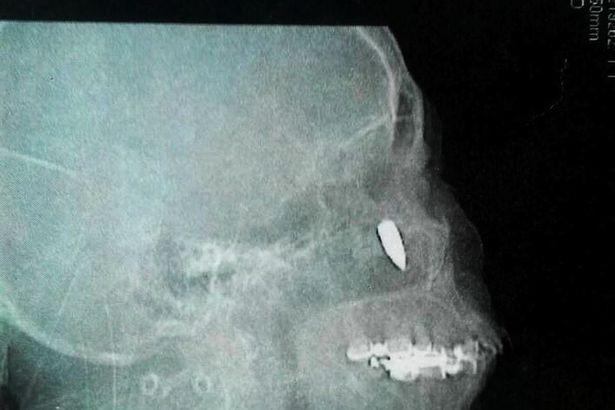

Ảnh chụp X-quang cho thấy viên đạn nằm sát sống mũi bệnh nhân.

Các bác sĩ đã chụp chiếu và phát hiện ra một viên đạn dài 2,5cm găm trong sống mũi bà Zhao 48 năm nhưng bà không hề hay biết.

Viên đạn có kích thước bằng một đồng xu.